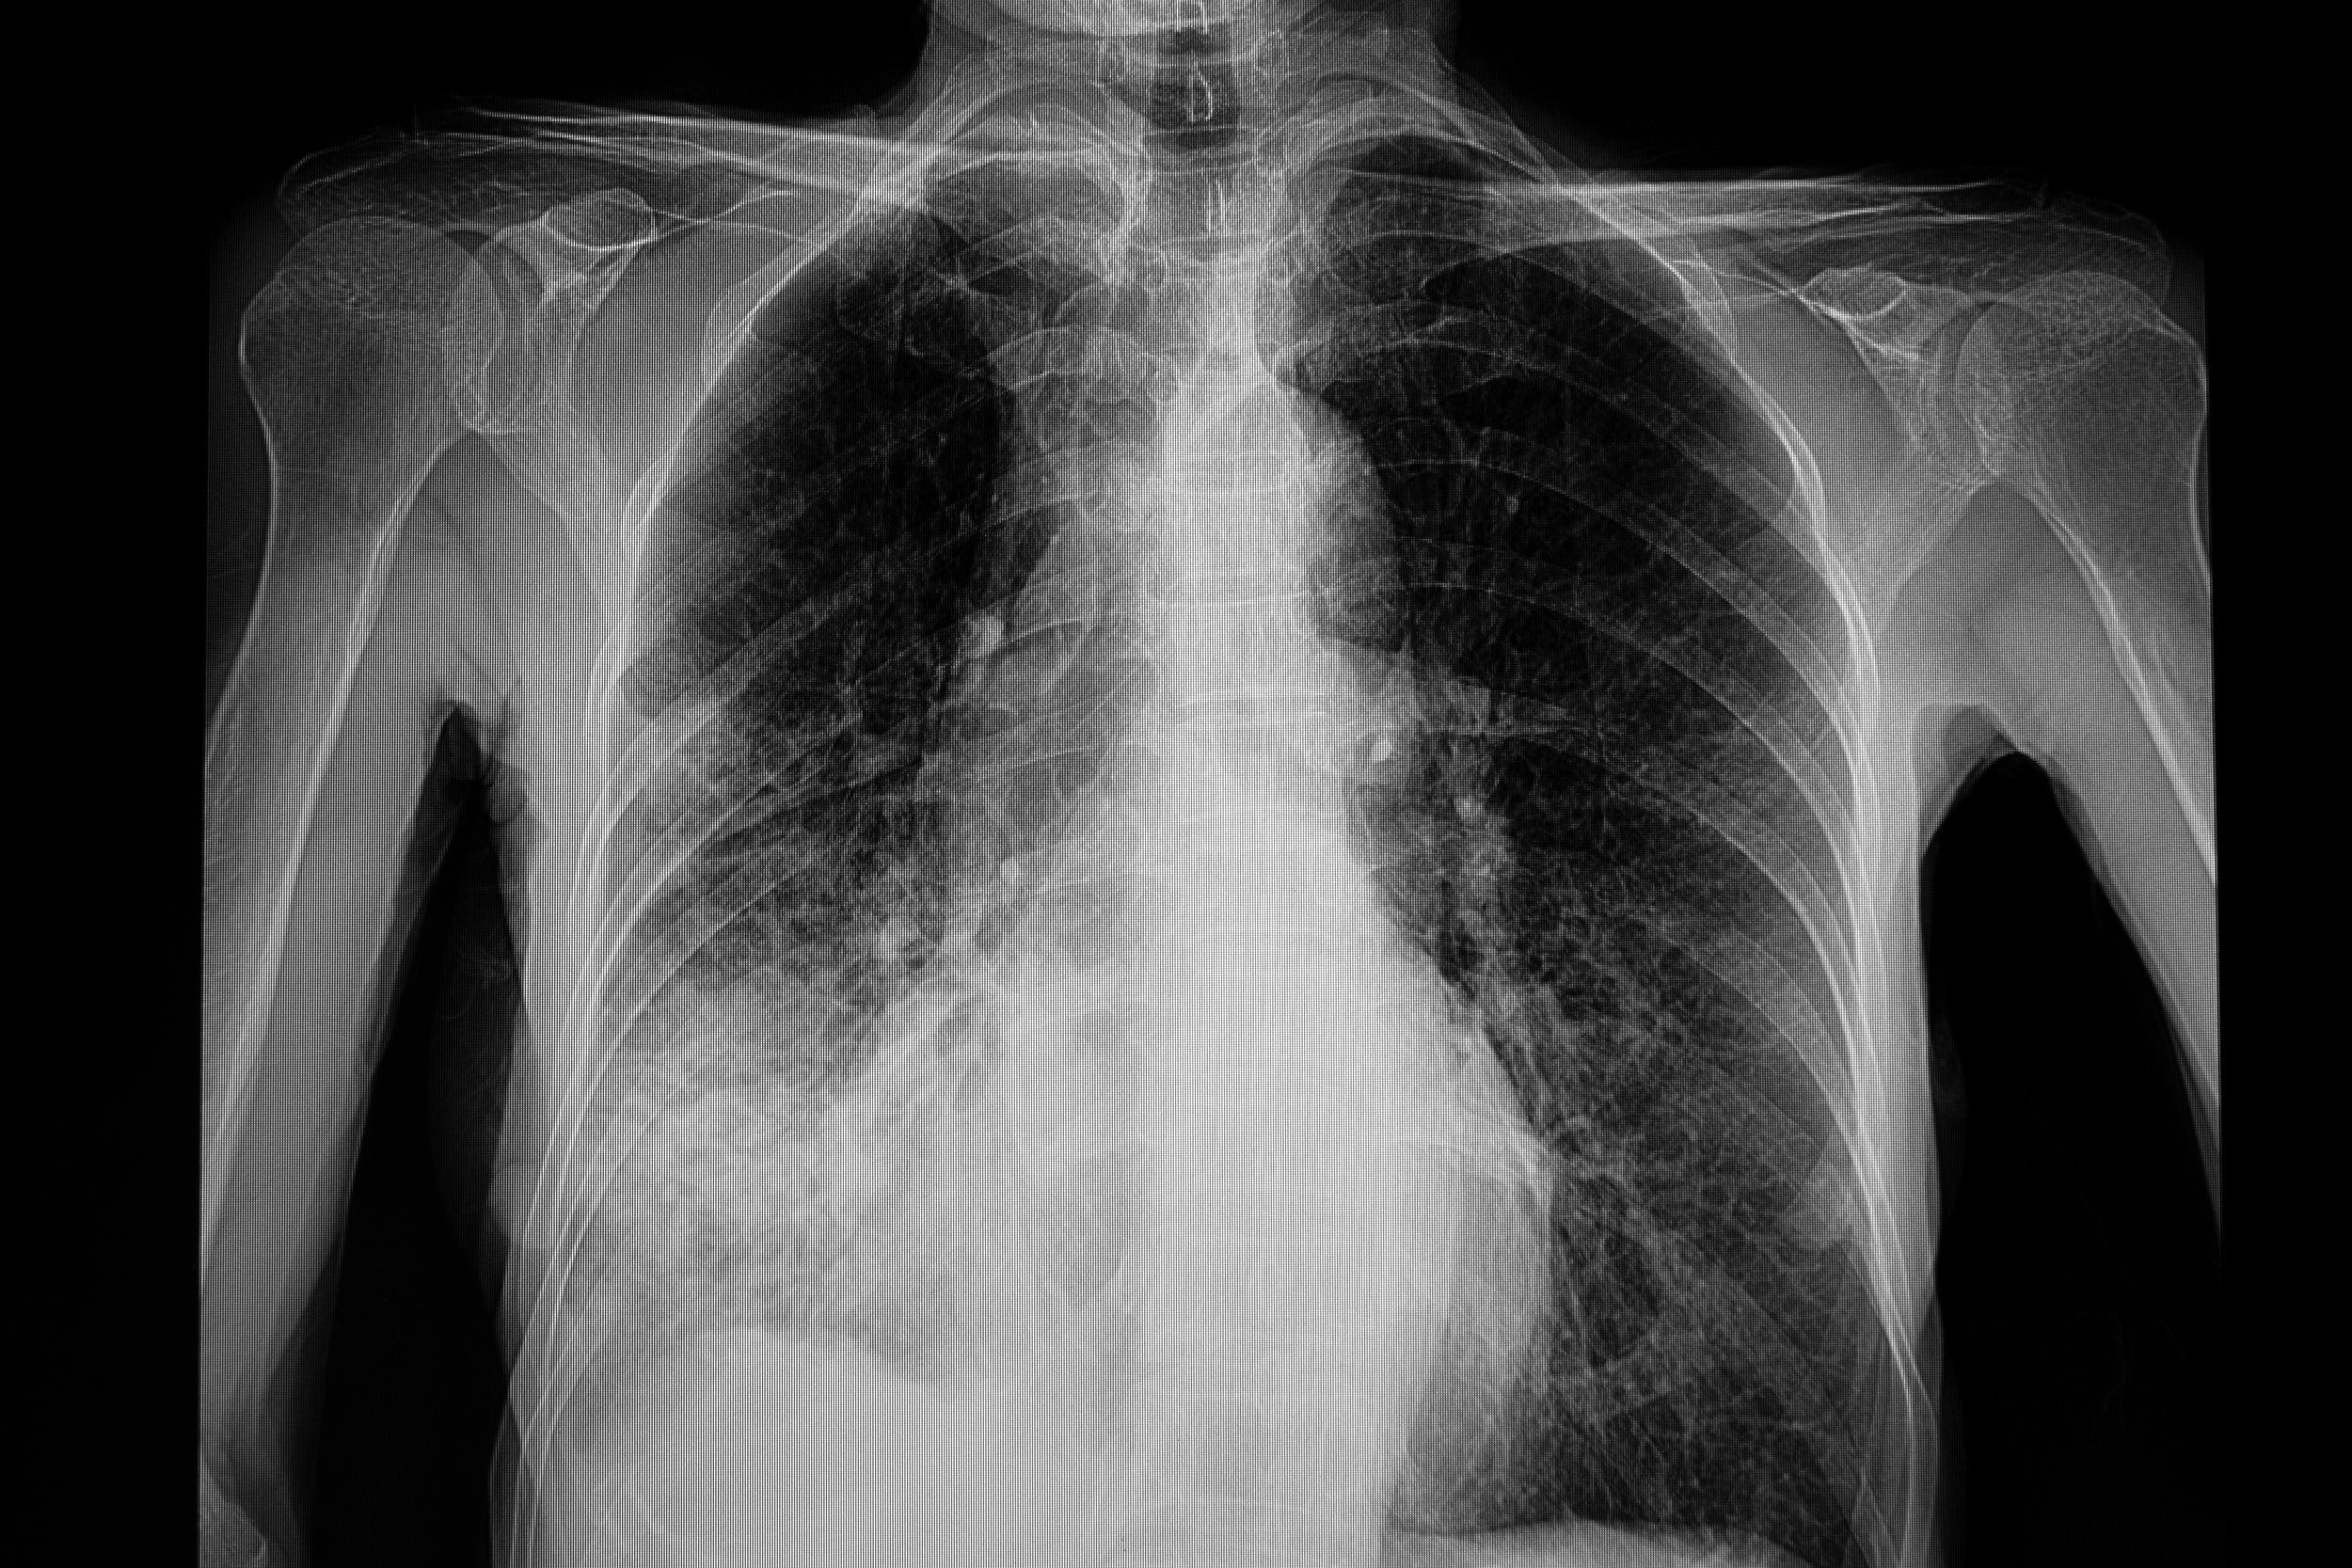

VIRAL ILLNESS headlines Norovirus causes up to 21 million illnesses in the U.S. every year. Here’s what to know about the contagious disease that hand sanitizer can’t kill Measles cases are mounting in the US as the UK declares a ‘national incident’ over the disease. What parents need to know to keep their kids safe pneumonia is the no. 1 cause of hospital admission in kids and adults. watch for these signs and symptoms What is ‘white lung’ pneumonia, and why is it reportedly on the rise in kids? What parents need to know